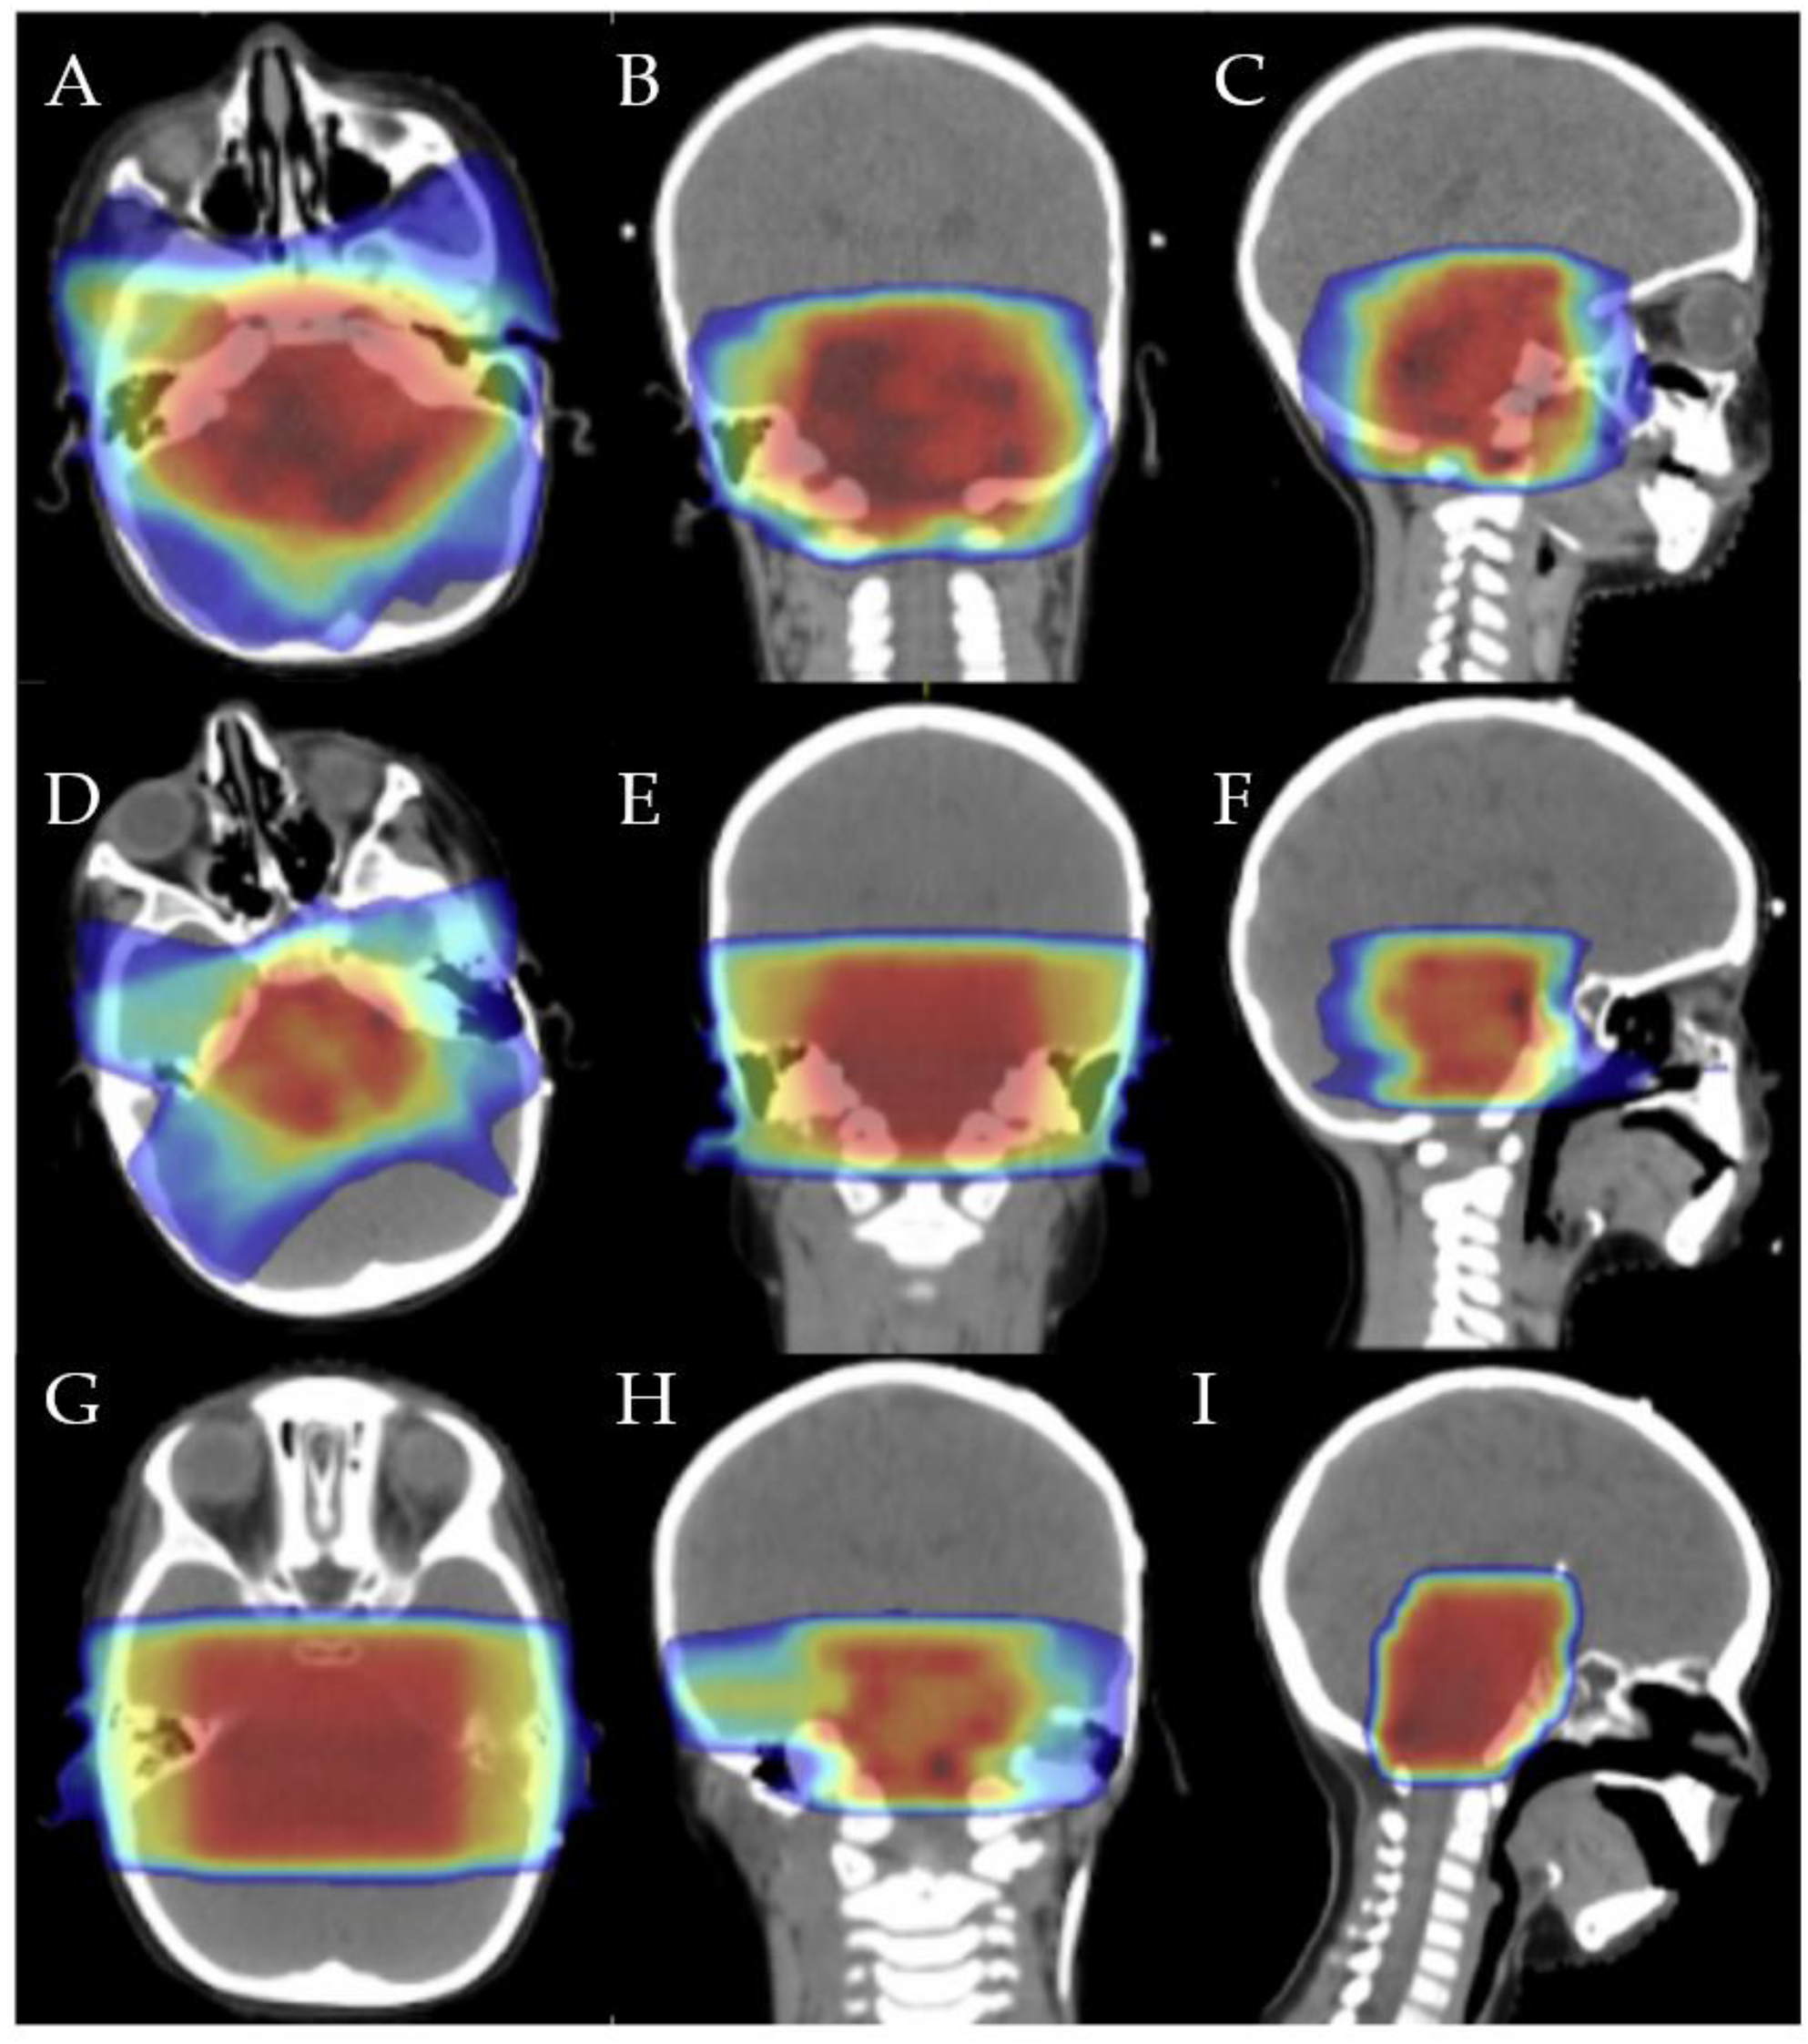

| Our experience | 2 Gy × 27 fx = 54 Gy | 1.8 Gy × 11 fx = 19.8 Gy | 2 Gy × 6 fx = 12 Gy | 85.5 Gy |